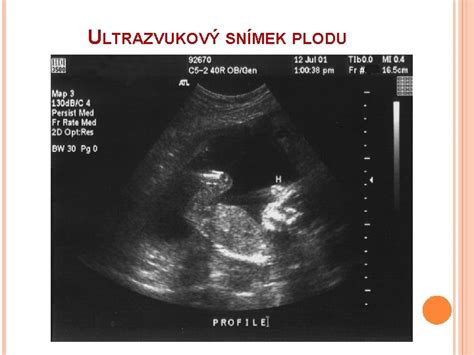

- Riziko pre plod: Sem patrí zhoršujúca sa vnútromaternicová rastová retardácia plodu alebo Rh izoimunizácia.